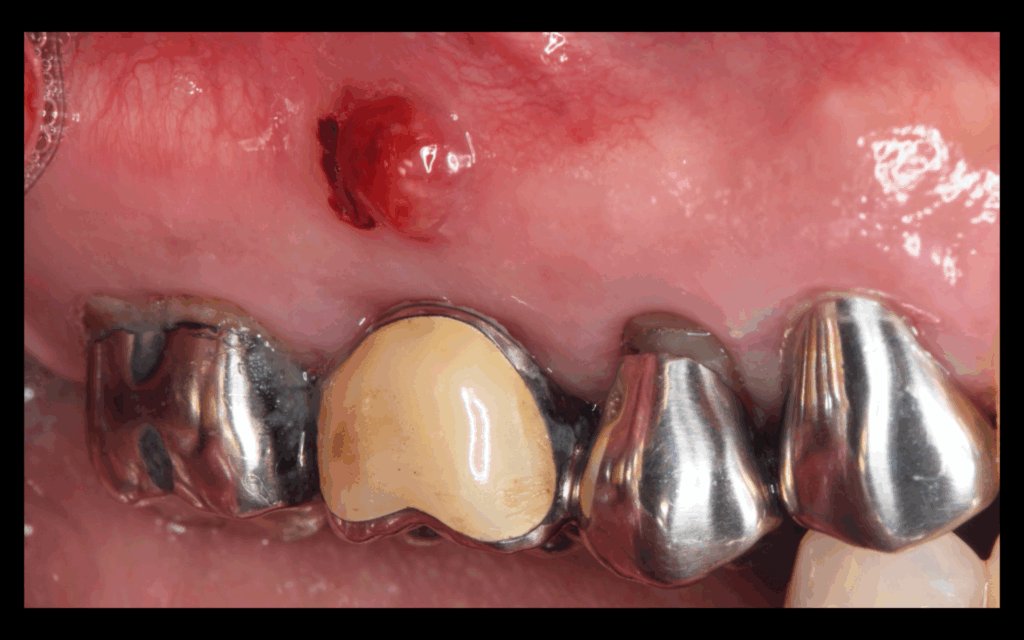

術中の写真。歯肉の中に埋まっていた歯を表に露出させた状態。赤い矢印がコンポジットレジン、黄色の矢印が表に出た歯となります。歯の縁を表に出した状態で補綴(被せ物)することは根管治療の予後にも影響します。